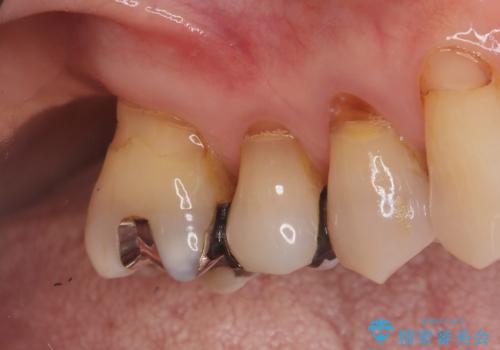

- 右上の奥歯(6番)が重度の歯周病により保存困難な状態であること、およびその後ろの7番もすでに失われていることを主訴にご来院されました。このままでは咬み合わせの機能が大きく低下してしまうため、抜歯後の早期回復と長期安定性を考慮し、インプラント治療を提案しました。治療計画は、

6番を抜歯すると同時にインプラントを埋入する抜歯即時埋入

失われた7番の部分にも同時にインプラントを埋入 の2本同時のインプラント埋入により、治療期間を短縮し、奥歯全体の機能再建を目指しました。

今回の治療では、まず重度歯周病の右上6番を慎重に抜歯し、その直後に6番と、すでに欠損していた7番の部分に、合わせて2本のインプラントを埋入しました。